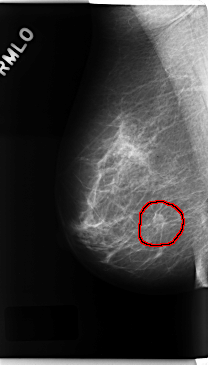

ics_version 1.0 filename C-0225-1 DATE_OF_STUDY 19 3 1997 PATIENT_AGE 55 FILM FILM_TYPE REGULAR DENSITY 2 DATE_DIGITIZED 14 4 1998 DIGITIZER LUMISYS LASER SEQUENCE LEFT_CC LINES 4744 PIXELS_PER_LINE 2512 BITS_PER_PIXEL 12 RESOLUTION 50 NON_OVERLAY LEFT_MLO LINES 4744 PIXELS_PER_LINE 2696 BITS_PER_PIXEL 12 RESOLUTION 50 NON_OVERLAY RIGHT_CC LINES 4736 PIXELS_PER_LINE 2728 BITS_PER_PIXEL 12 RESOLUTION 50 OVERLAY RIGHT_MLO LINES 4736 PIXELS_PER_LINE 2712 BITS_PER_PIXEL 12 RESOLUTION 50 OVERLAY |

FILE: C_0225_1.RIGHT_MLO.OVERLAY TOTAL_ABNORMALITIES 1 ABNORMALITY 1 LESION_TYPE MASS SHAPE OVAL MARGINS SPICULATED ASSESSMENT 5 SUBTLETY 5 PATHOLOGY MALIGNANT TOTAL_OUTLINES 1 BOUNDARY |